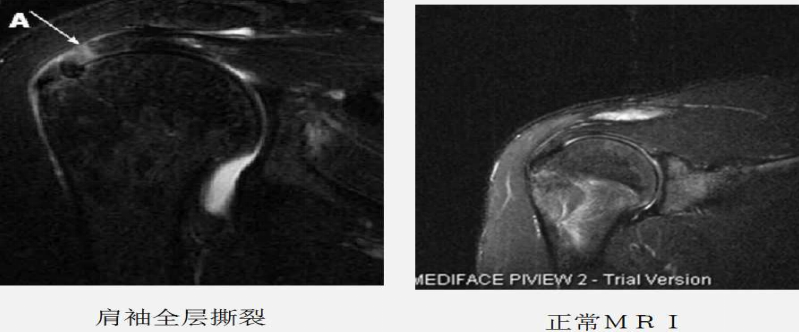

磁共振及磁共振关节造影:MRI是目前检查肩袖损伤最有效的影像学方法。MRI通过形态和信号的异常反应可显示肩袖损伤的各期表现。磁共振关节造影是在透视下经关节囊内注射含碘造影剂。由于关节囊的扩张,微小的肩袖撕裂在造影剂的衬托下显示得更为清楚,磁共振关节造影的准确率超过90%。